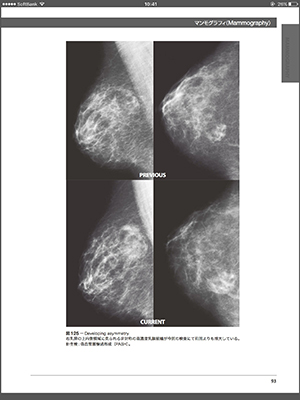

BI-RADS®は,乳がん画像診断の用語などの標準化と精度管理を目的にACR(American College of Radiology)が発刊したマンモグラフィのガイドライン。

日本語版は ACR BI-RADS® 翻訳中央委員会によって翻訳が進められ,マンモグラフィ,超音波,MRIの3部により構成されている。